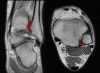

1. Anterior Talofibular ligament

Coronal (left) and axial (right) T1W images assessing the normal normal anterior talofibular ligament.